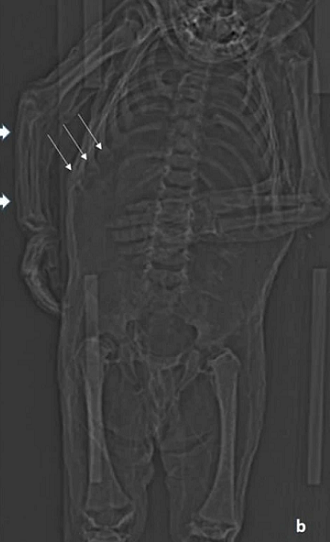

Tuy nhiên, kết quả chụp CT thể hiện xương sườn của cậu bị biến dạng, dấu hiệu của căn bệnh chuyển hóa xương (Metabolic Bone Disease - MBD) thường được thấy trong các trường hợp mắc bệnh còi xương nghiêm trọng. Hình ảnh chụp cắt lớp cũng cho thấy tình trạng đặc trưng của bệnh viêm phổi.

Đối với các nhà nghiên cứu, điều này cho thấy rằng mặc dù đứa trẻ mới biết đi đã được cho ăn đủ để tăng cân nhưng vẫn bị suy dinh dưỡng, hậu quả của việc bị giữ trong nhà không cho tiếp xúc với ánh nắng mặt trời khiến cơ thể cậu bé bị thiếu vitamin D.

Với những bằng chứng thu thập được, nhóm nghiên cứu kết luận rằng, cậu bé đã chết vì bệnh viêm phổi cũng như cơ thể thiếu hụt những nguồn dinh dưỡng cần thiết.